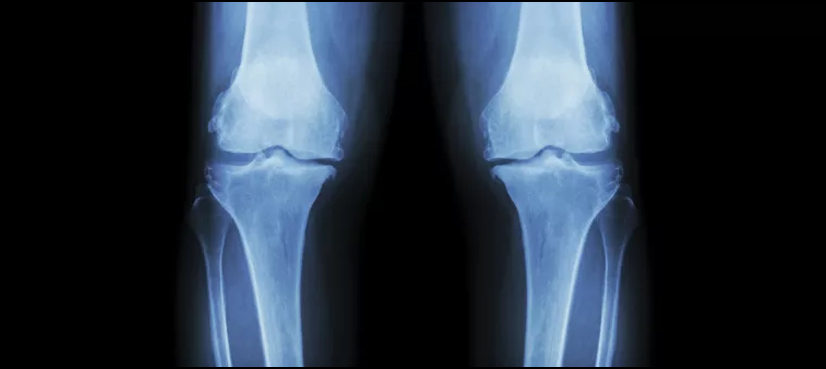

NEW YORK: Many older adults are getting surgery to remove damaged cartilage in the knee even though these operations may not help ease pain or improve mobility in people over 65, a U.S. study suggests.

Researchers focused on a procedure known as arthroscopic partial meniscectomy, which involves shaving or cutting out damaged or torn tissue. Some previous research suggests younger patients with severely damaged cartilage may benefit from this operation, but it may not work any better than physical therapy for most people, especially when they’re over 65, researchers note in JAMA Surgery.